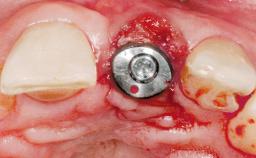

Immediate Flapless Placement of an Implant in a Maxillary Right Lateral Incisor Site

This 43-year-old male patient, a non-smoker, came to our practice because of a fracture of tooth 12 caused by a bicycle accident. Due to the combined para- and infrabony crown and root fracture, tooth extraction, and subsequent implant placement were suggested to the patient as the therapy of choice. The patient had high esthetic expectations with regard to the treatment outcome and asked for an immediate fixed provisional restoration. His individual esthetic risk profile summed up to a medium esthetic risk.